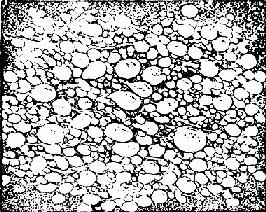

来源于胚胎的滋养细胞。由于绒毛水肿增大,形成大小不等的水泡,相连成串,状似葡萄,故称葡萄胎(图167)。

水泡状胎块

图167 水泡状胎块